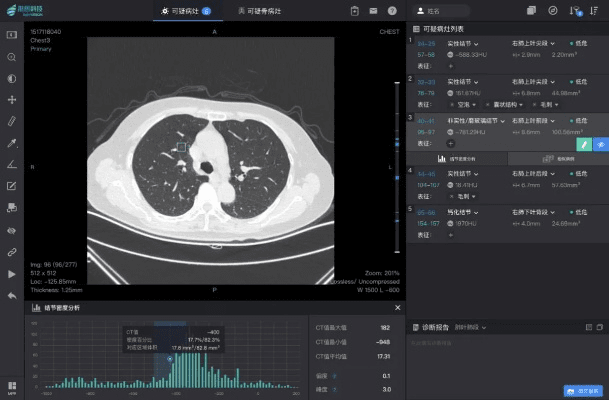

官方669下载 下载,实地设计评估解析 CT_v1.636

在追求专业效率和精准执行的现代工作环境中,我们欣然介绍一款能够为专业人士、高级玩家和企业用户提供卓越服务的应用——CT_v1.636,作为一款行业标准和强大工具,它以其高级功能、可定制性和强大的输出能力,成为市场上备...